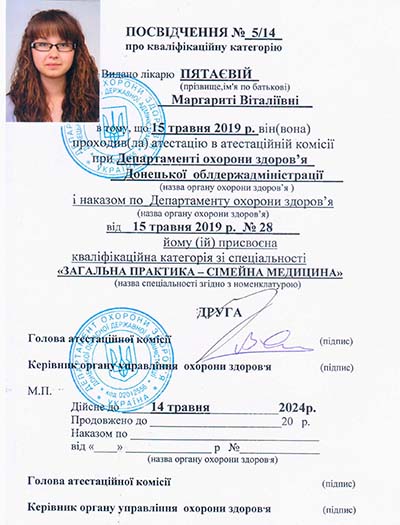

Лицензии и сертификаты

Лечение в нашей клинике анонимно, поэтому никто не узнает, что вы проходите или проходили лечение в нашем наркологическом центре.

Лицензии и сертификаты нашей клиники

Медицинские услуги оказываются ООО "ЮгЭкоСервис+" по лицензии ЛО-61-01-008143 от 28.12.2021 г.